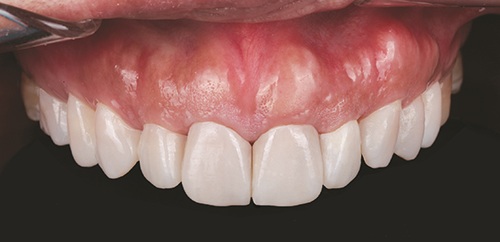

The final restorations effectively masked the tetracycline staining and met the patient’s aesthetic expectations (Figs. 9–11). The patient was recalled for evaluation one week post-insertion, and again two weeks later for delivery of a custom night guard to protect the restorations.

Fig. 9: Post-op full smile

Fig. 10

Fig. 11

The final restorations demonstrated favorable aesthetic and functional outcomes. The veneers provided the planned masking of the discoloration and reflected natural surface texture and translucency. At follow-up, the restorations showed stable function and integration, and the patient reported satisfaction with the result. The potential for future removal or revision was discussed and documented as part of the informed-consent process.